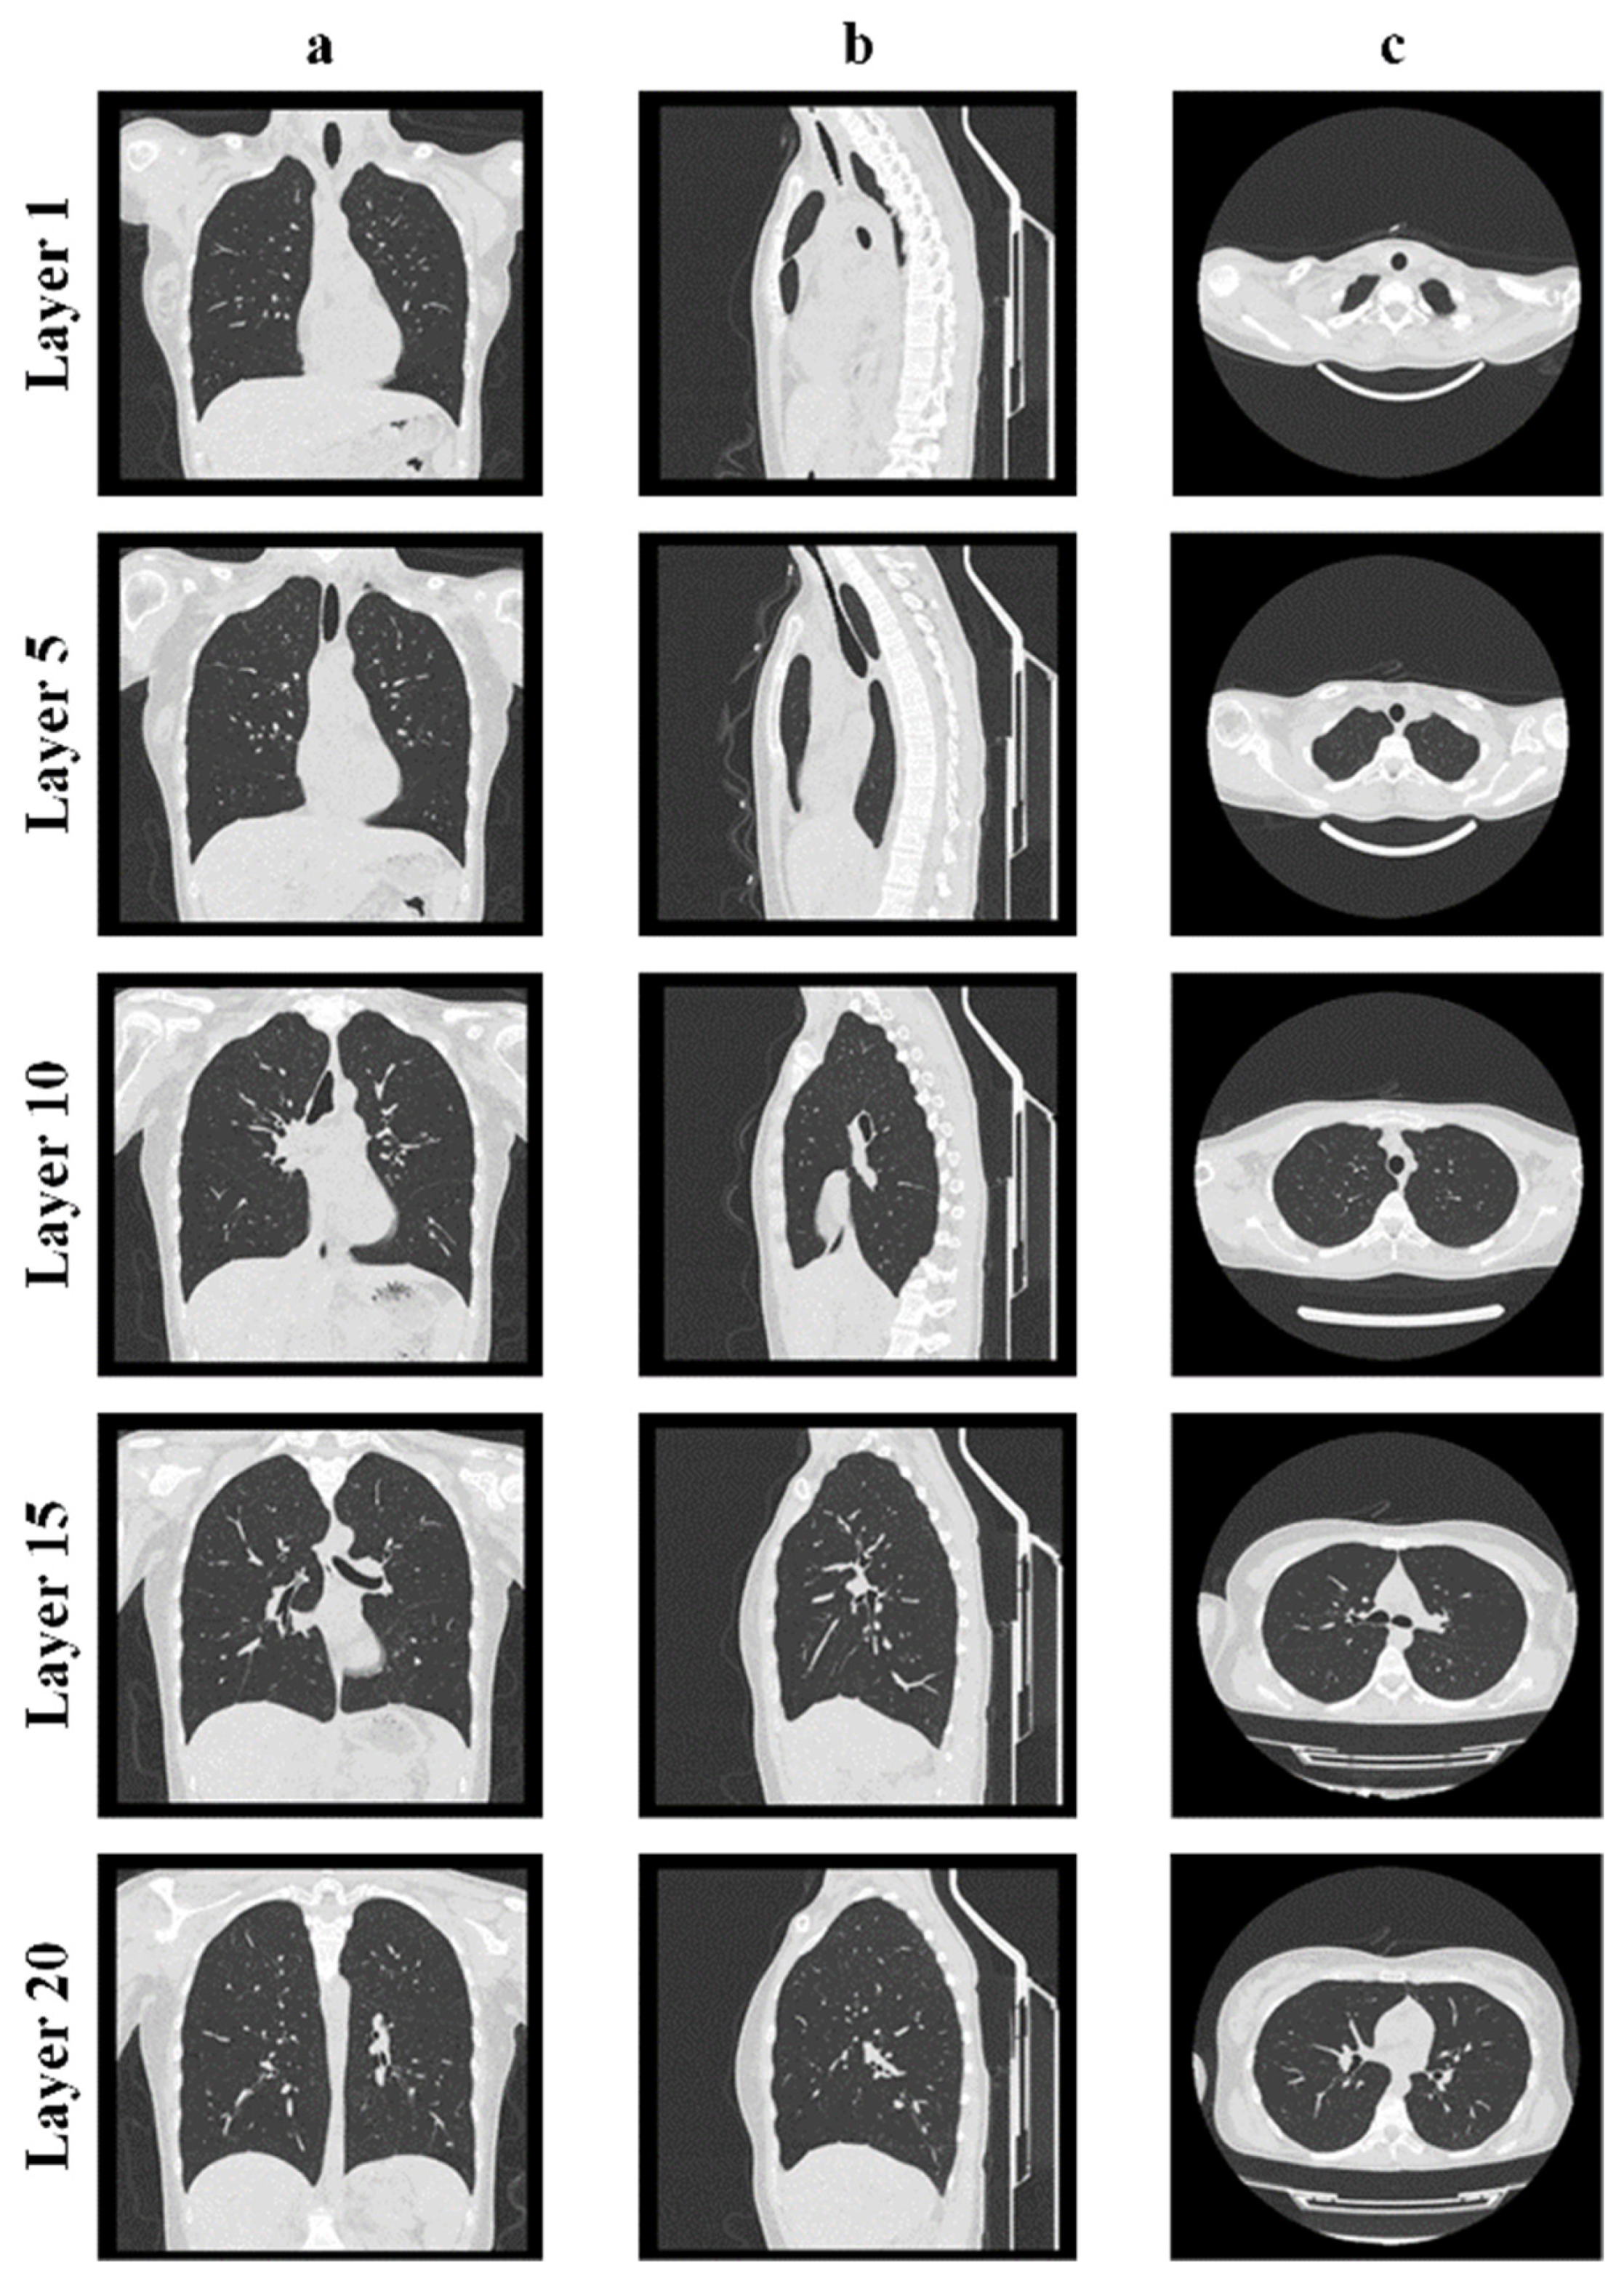

Figure 2 shows the obtained CT results for the lower respiratory tract (human lungs) in three different projections.

The CT images above clearly show the boundaries between the airways (dark area of the CT images) and soft or bone tissue (light area of the CT images).

Figure 2. CT results of human lungs: coronal plane (a); sagittal plane (b); axial plane (c).